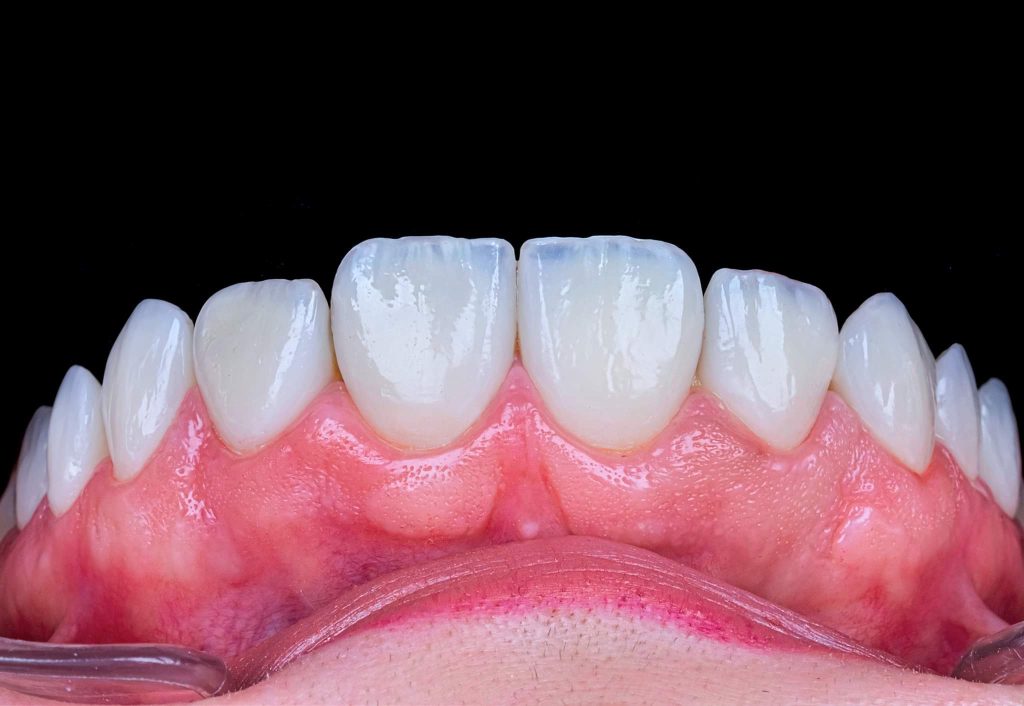

The case presented in this case report is for a 27-years-old female patient with a chief complaint of aesthetic correction for her smile. The patient was unhappy with her smile. After clinical examination, there were previous old composite veneering done poorly and incorrectly to close the multiple interdental spacing. After discussing the various treatment options (i.e., orthodontic treatment, direct, or indirect veneers), indirect ceramic veneering was selected. The step-by-step treatment protocol is presented in the images below.